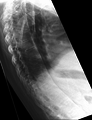

-

Lateral X-ray of the mid back in ankylosing spondylitis